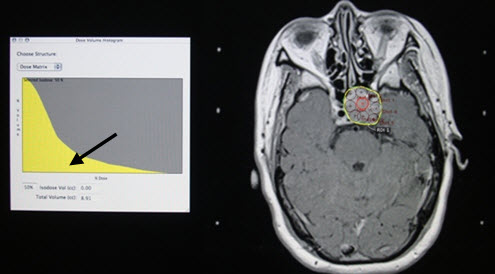

Hình 2. Đặt các trường chiếu (shot) đảm bảo phủ kín hết khối u.

Dưới đây minh họa một số hình ảnh lập kế hoạch xạ phẫu với dao gamma quay cho u tuyến yên trên hình ảnh MRI (hình 1, 2, 3).